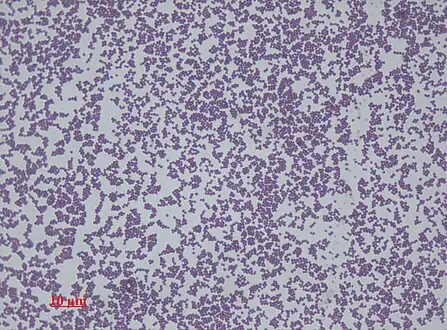

Staphylococcus epidermidis is a very hardy microorganism, consisting of nonmotile, Gram-positive cocci, arranged in grape-like clusters. It forms white, raised, cohesive colonies about 1–2 mm in diameter after overnight incubation, and is not hemolytic on blood agar.[5] It is a catalase-positive,[7] coagulase-negative, facultative anaerobe that can grow by aerobic respiration or by fermentation. Some strains may not ferment.[3][8]

Staphylococcus epidermidis, 1000 magnification under bright field microscopy